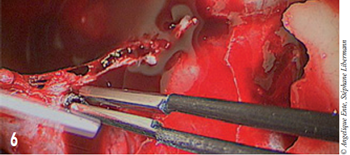

L’hémostase est effectuée à l’aide d’une pince bipolaire (figure 6).

Figure 6 – Hémostatse à l’aide d’une pince bipolaire.